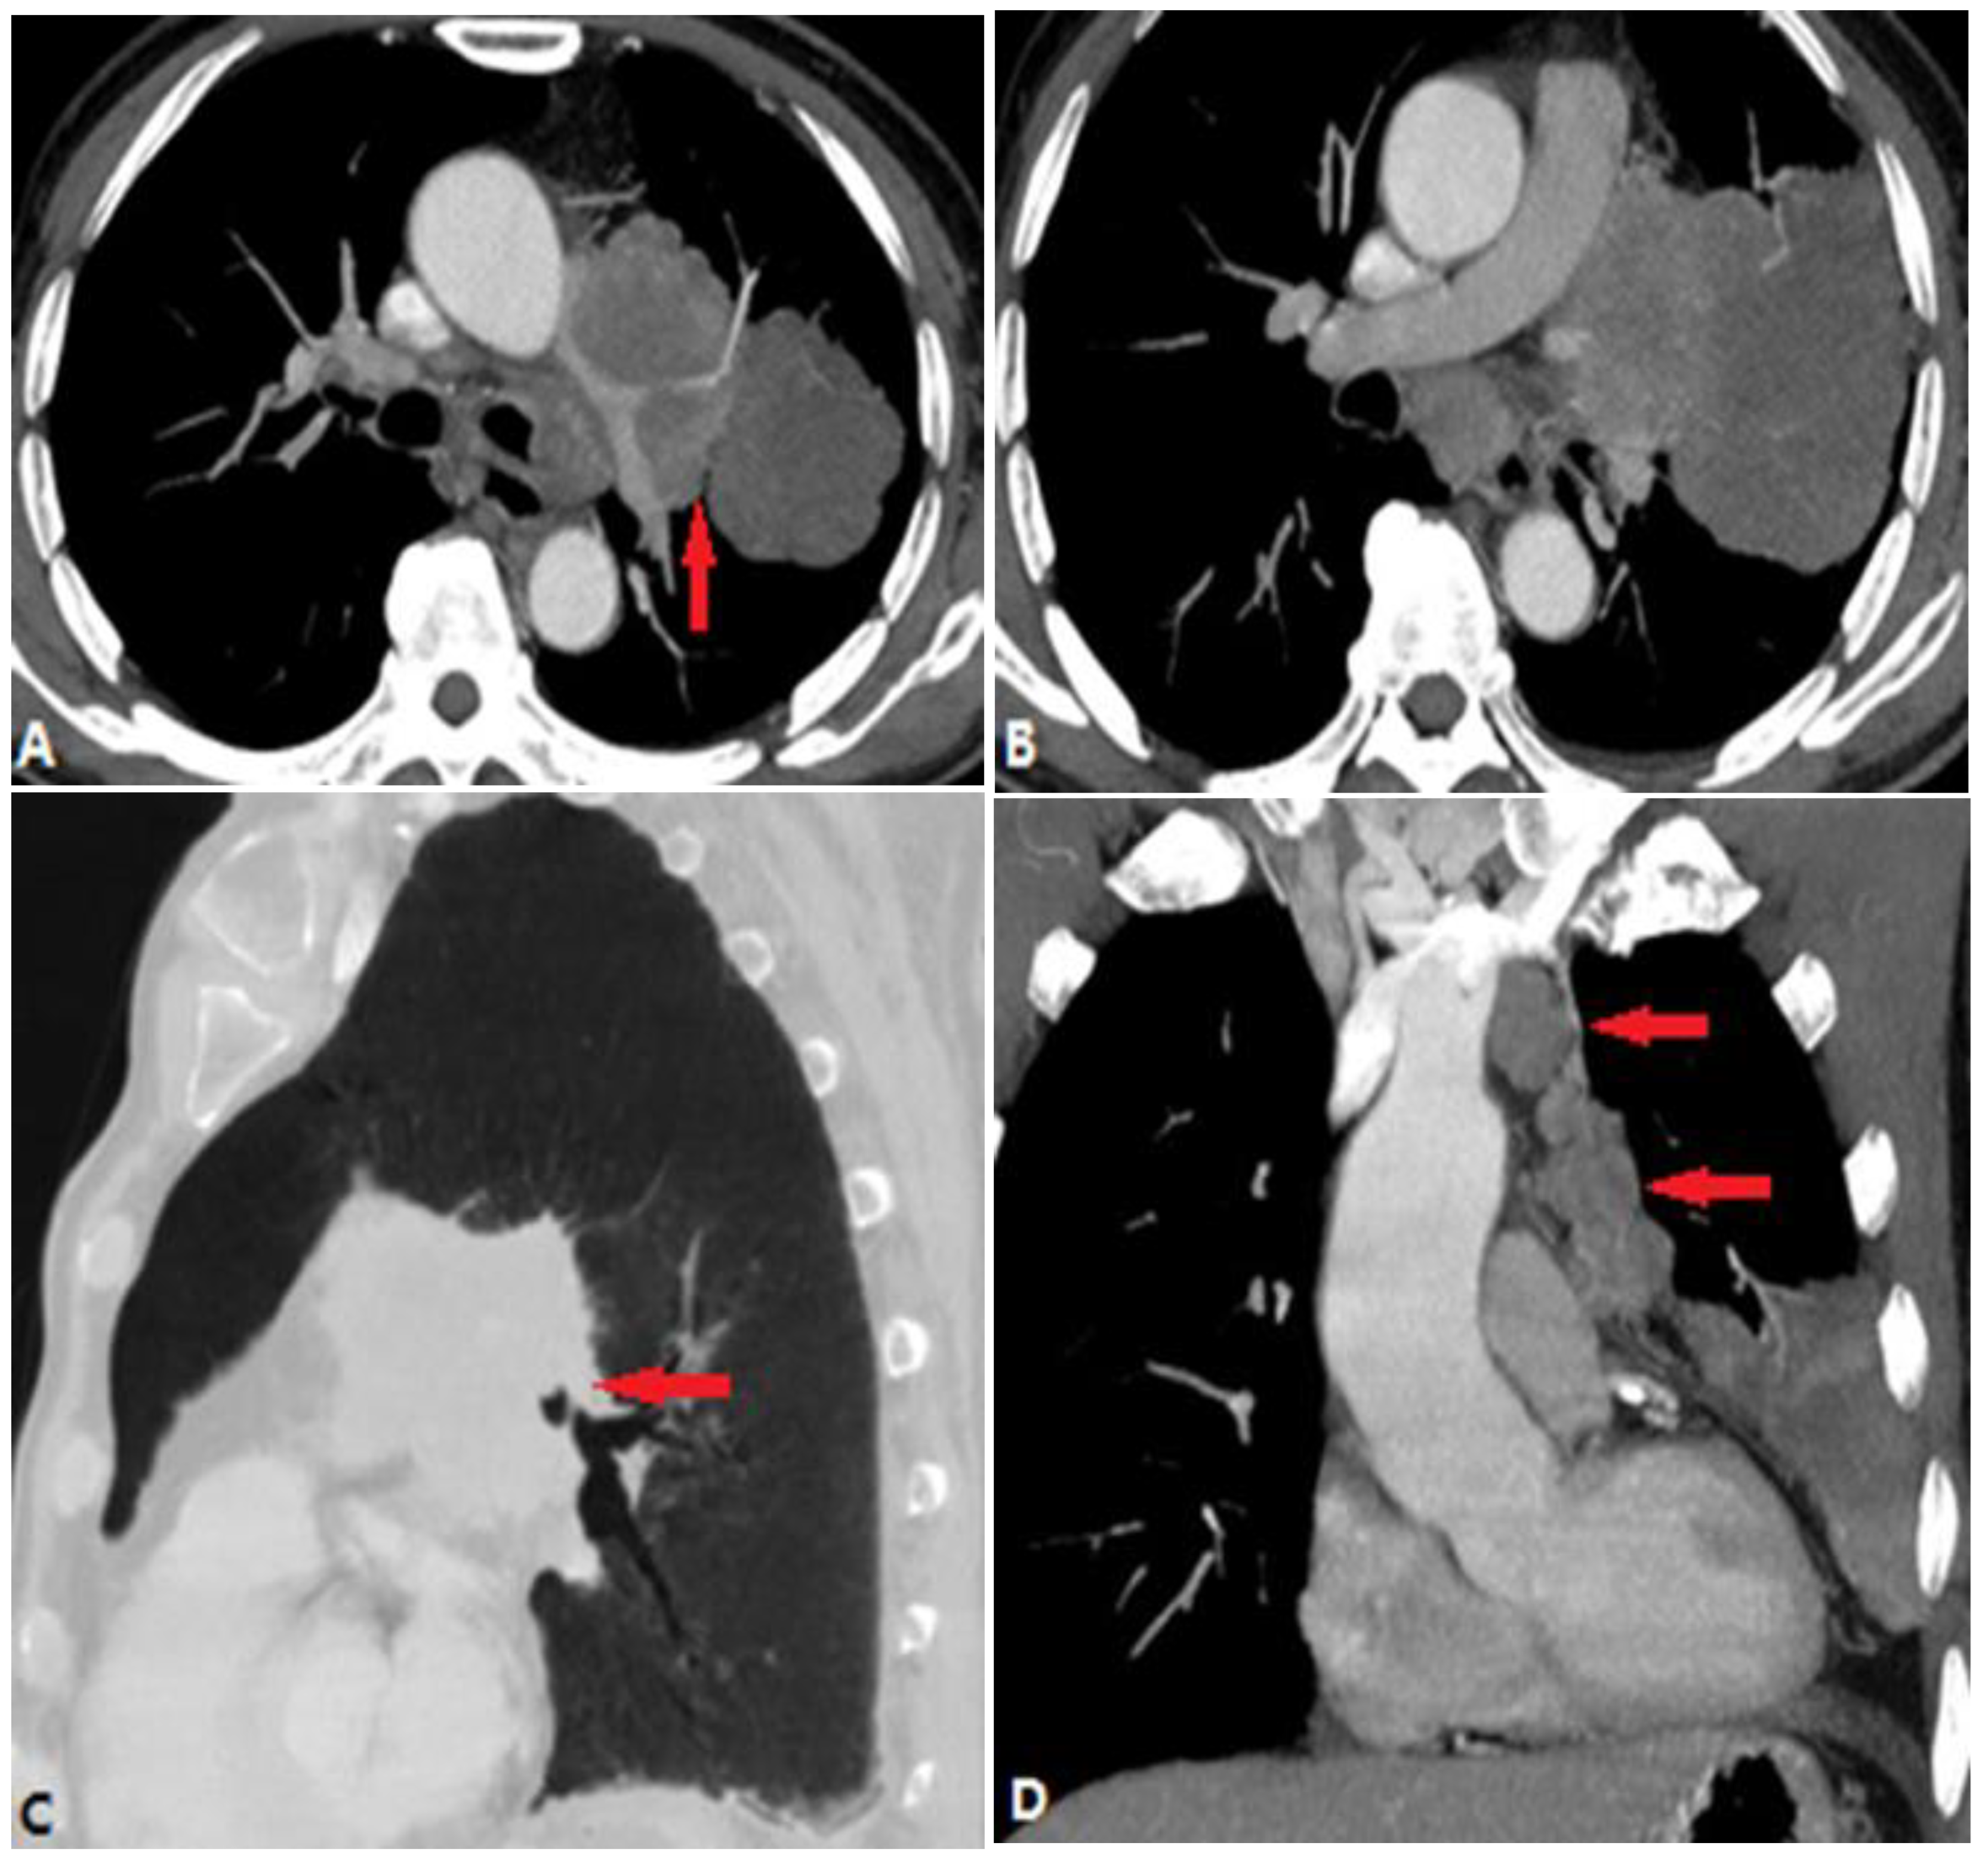

4.3.1. Fibrosis Mediastinitis (FM)

4.3.2. Tumors Causing Pulmonary Artery Stenosis